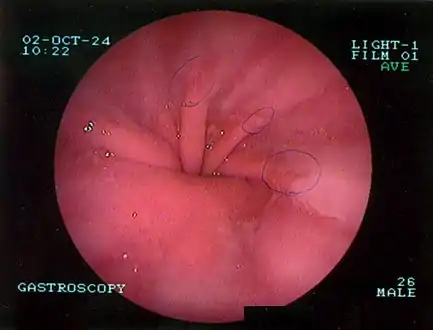

Diagnosis

The diagnosis of a hiatal hernia is typically made through an upper GI series, endoscopy, high resolution manometry, esophageal pH monitoring, and computed tomography (CT). Barium swallow as in upper GI series allows the size, location, stricture, stenosis of oesophagus to be seen. It can also evaluate the oesophageal movements. Endoscopy can analyse the esophageal internal surface for erosions, ulcers, and tumours.

Meanwhile, manometry can determine the integrity of esophageal movements, and the presence of esophageal achalasia. pH testings allows the quantitative analysis of acid reflux episodes. CT scan is useful in diagnosing complications of hiatal hernia such as gastric volvulus, perforation, pneumoperitoneum, and pneumomediastinum.[8]